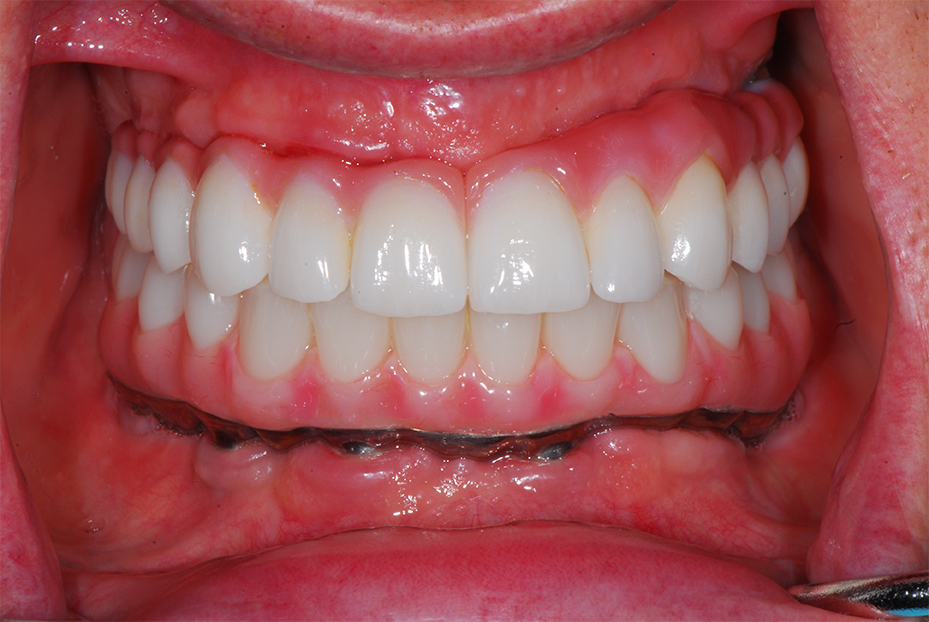

Full mouth implant reconstruction with an upper full arch zirconia bridge supported on six implant fixtures, and a lower full arch titanium framework acrylic bridge, also on six implant fixtures.

After